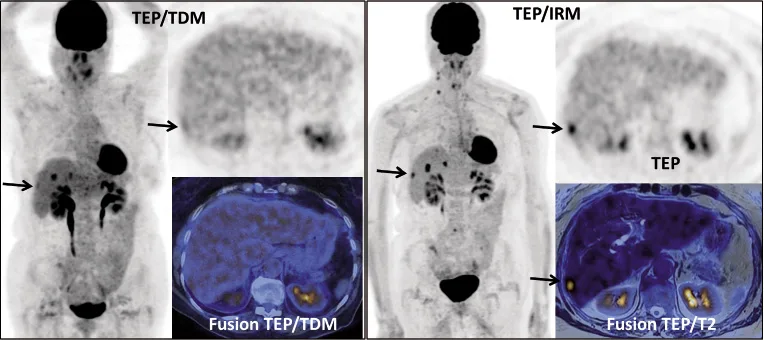

Figure 3a. Femme de 75 ans. Cancer colorectal (T3N1M0) traité par chirurgie et chimiothérapie. Bilan de récidive hépatique. Réalisation d’un TEP/TDM suivi d’un TEP/IRM. Le TEP/TDM montre plusieurs fixations hépatiques. Le TEP/IRM permet de préciser l’étendue de l’atteinte hépatique, en montrant clairement une lésion sous capsulaire du secteur postérieur du foie droit, très mal visualisée sur le TEP/TDM (flèche)

Figure 3b. Même patiente. Coupes transversales au niveau du dôme hépatique. Le TEP/TDM apparaît normal à ce niveau. Le TEP/IRM montre deux fixations focales de petite taille, dont le caractère pathologique est difficile à affirmer. Une séquence de diffusion montre clairement deux hypersignaux pathologiques en regard des deux hyperfixations. La confrontation du TEP et de la diffusion permet de renforcer la confiance dans le diagnostic de métastases hépatiques à ce niveau

Figure 4a. Femme de 62 ans. Bilan d’extension initial d’un carcinome séreux de l’ovaire. Le TEP/TDM montre des fixations en rapport avec une carcinose péritonéale pelvienne et du grand épiploon (flèches). Le TEP/IRM réalisé juste après le TEP/TDM montre des sites supplémentaires d’atteinte péritonéale, dans la région péri-hépatique et la gouttière pariéto-colique gauche (flèches)

Figure 4b. Même patiente. Coupes transversales au niveau du dôme hépatique. Le TEP/TDM ne montre pas d’anomalies à ce niveau. Le TEP/IRM montre clairement l’ascite et des fixations anormales sur la coupole diaphragmatique, bien visibles aussi sur les séquences de diffusion (flèches). L’excellent recalage entre TEP et IRM, du fait de l’acquisition simultanée et la concordance des anomalies, renforcent le degré de confiance diagnostique